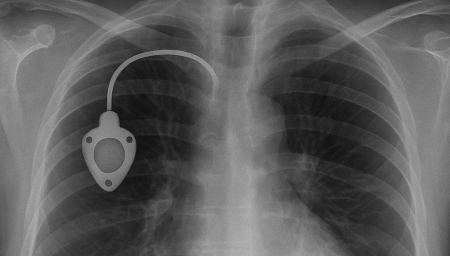

항암관(Chemoport)삽입

Chemoport는 항암제처럼 자극이 강한 약물을 안전하고 안정적으로 투여하기 위해 흉부 피부 아래에 이식하는 중심정맥 사용 포트입니다. 팔 혈관이 약하거나 반복 주사로 인한 통증이 걱정되는 환자에게 도움을 줄 수 있으며, 장기간 치료가 필요한 경우 편안하게 항암 치료를 지속할 수 있도록 설계되어 있습니다.

항암관(Chemoport)삽입 과정

국소마취 후 작은 절개를 시행 (보통 쇄골 아래 약 2~3cm 정도 절개)

정맥에 카테터 삽입 후 포트와 연결

방사선으로 카테터 위치 확인

피부 봉합 후 소독 드레싱